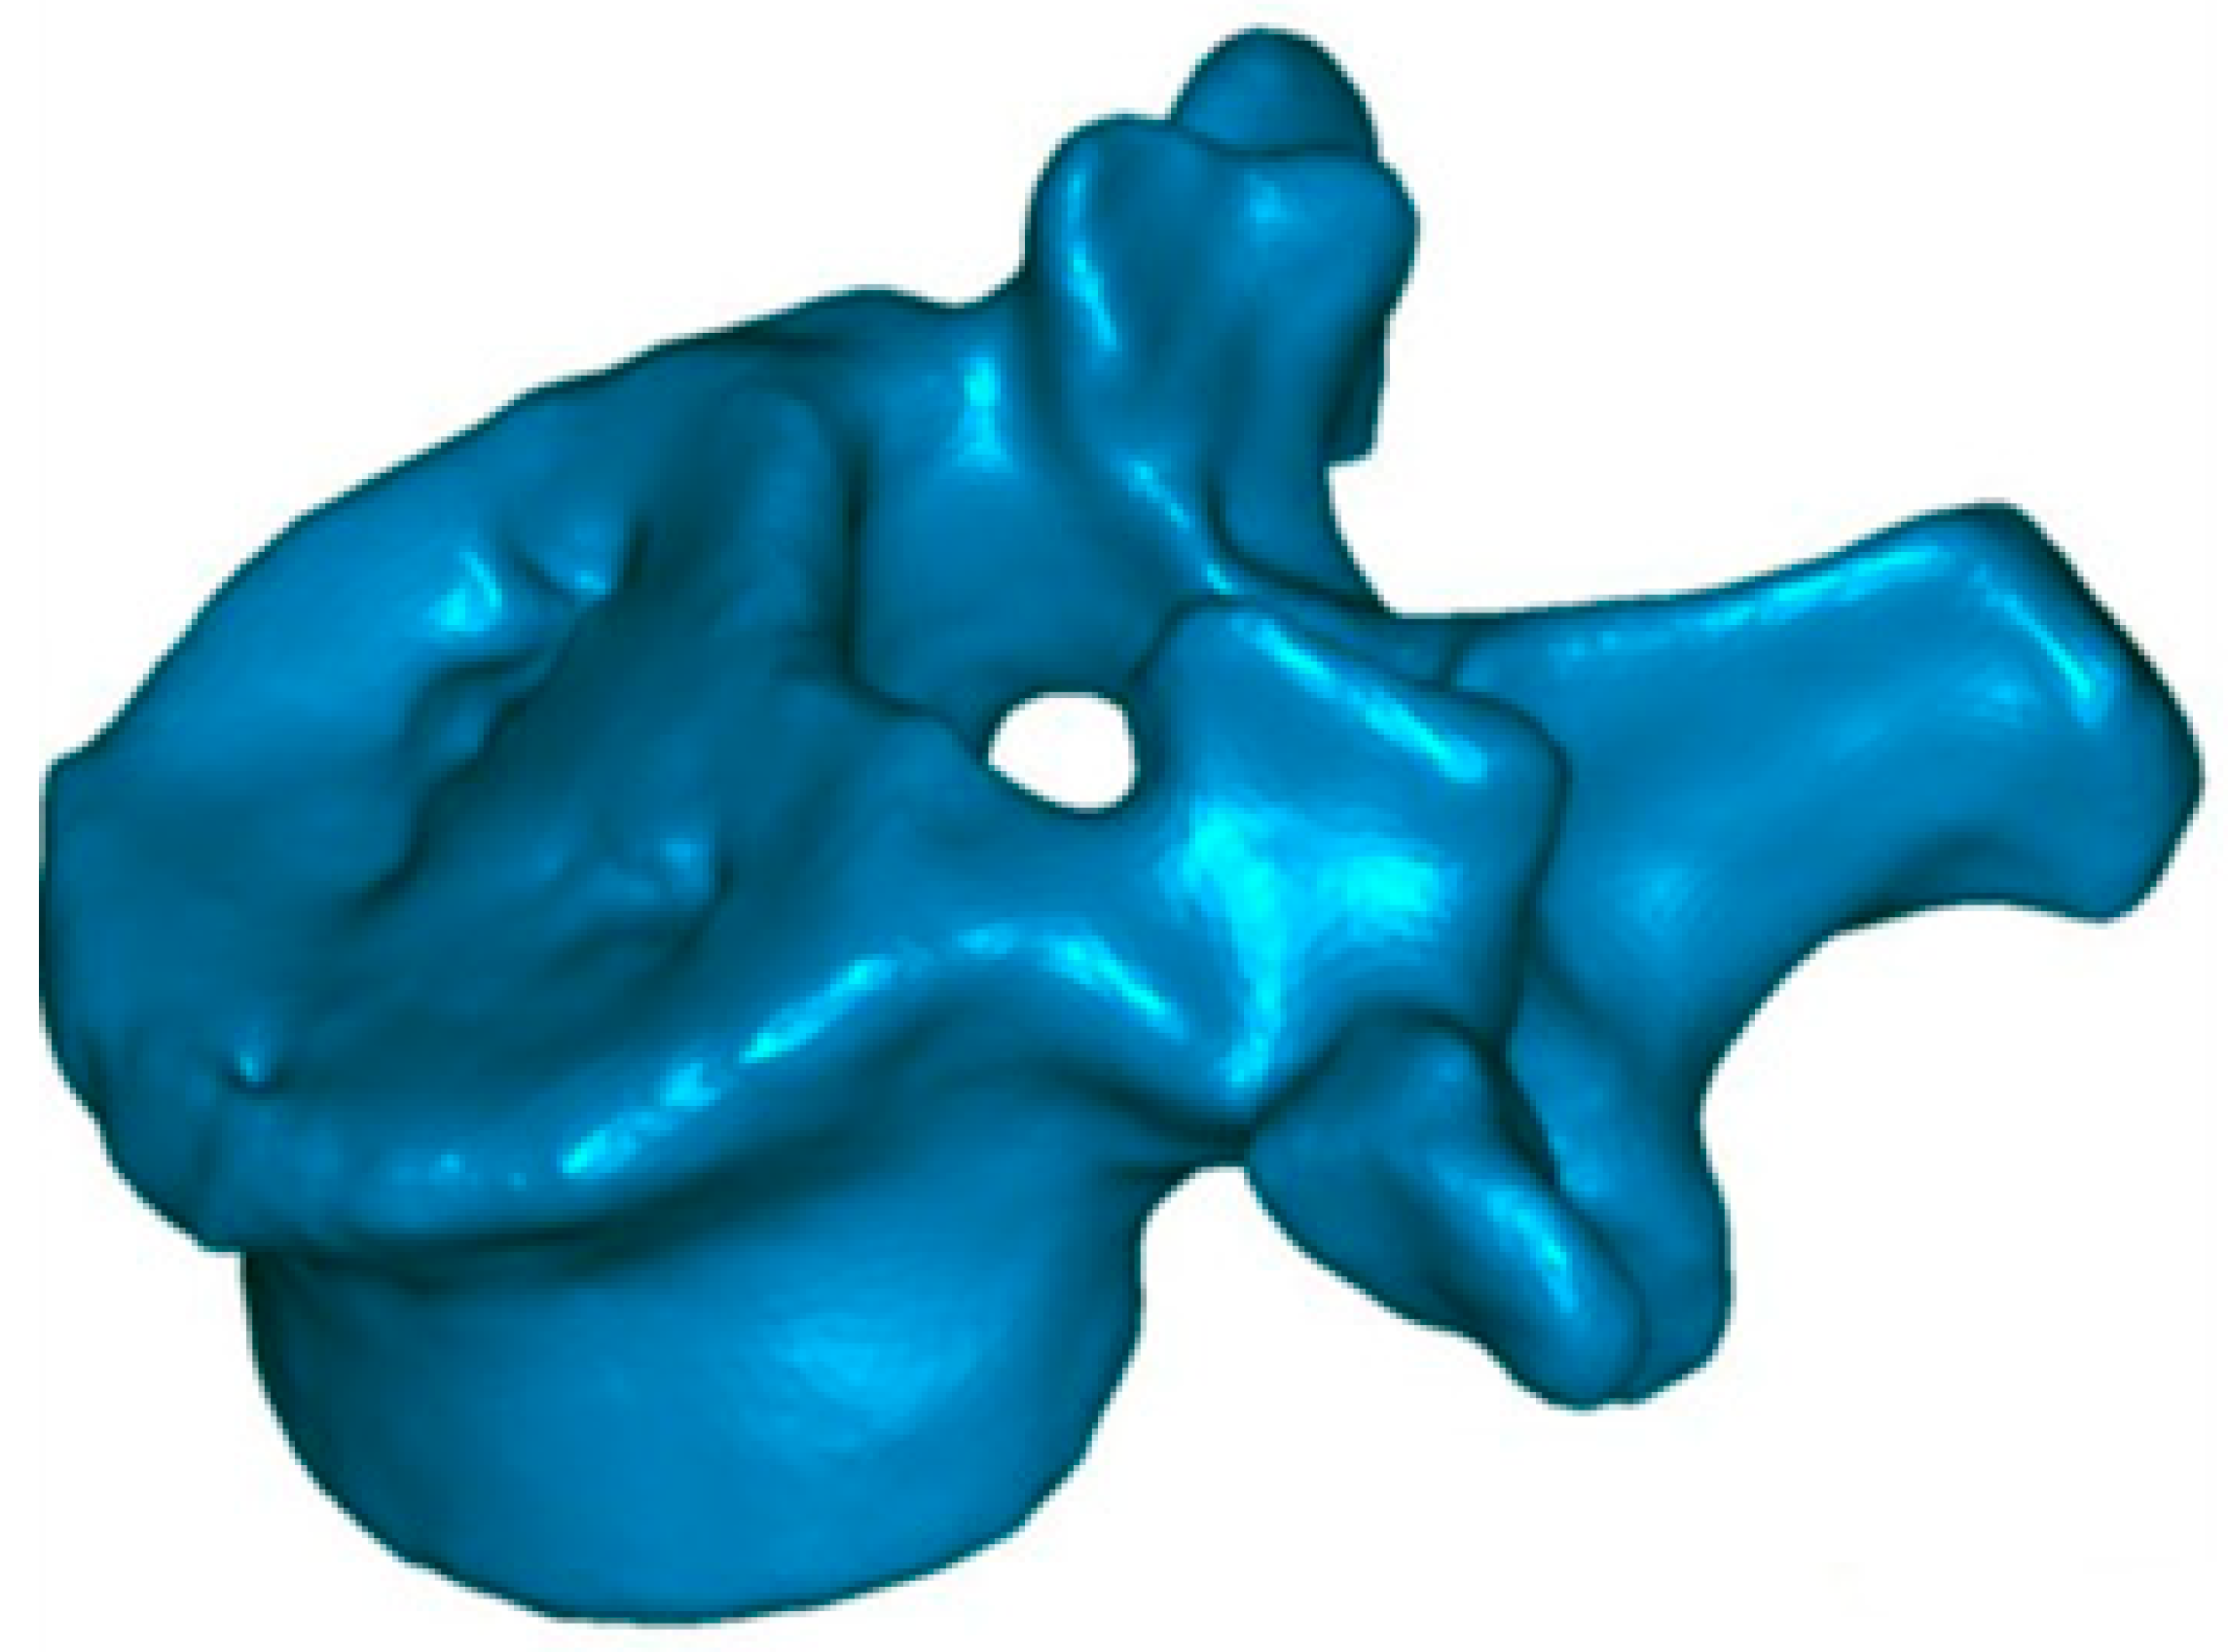

2.2. Evaluation of Anatomical Restoration

To know the vertebral height restoration in fractures after vertebroplasty, there exists no unanimous methodology. Moreover, existing methods are imprecise and can lead to great variability. Therefore, it is necessary to define a method that can be used to evaluate anatomical restoration. In our study, we have used 3D technology, that is definitive in this proposed new treatment [12,18,37]. The method has been developed by LBM ENSAM (Paris, France) to quantify the anatomical restoration. The exploration and interventions were carried in the Hospital Clínico Universitario de Valladolid. We have used a system: Revolution General Electric spectral CT, Healthcare. The protocol to be followed was based on the following parameters: tube voltage: between 80 and 140 kVp, milliamperage: 190 mA, rotation time: 0.8 s, pitch: 0.516, slice thickness: 0.625 mm, ASIR-V-40%, ASIR-V-40% and ASIR-V-40%. From millimetre axial slices of CT scans, 3D reconstructions were obtained using a segmentation technique (Figure 1 and Figure 2).

Figure 1.

Preoperative 3D reconstruction. Sinking of the entire upper vertebral endplate (red arrow), with involvement of the cortical ring (blue arrow).